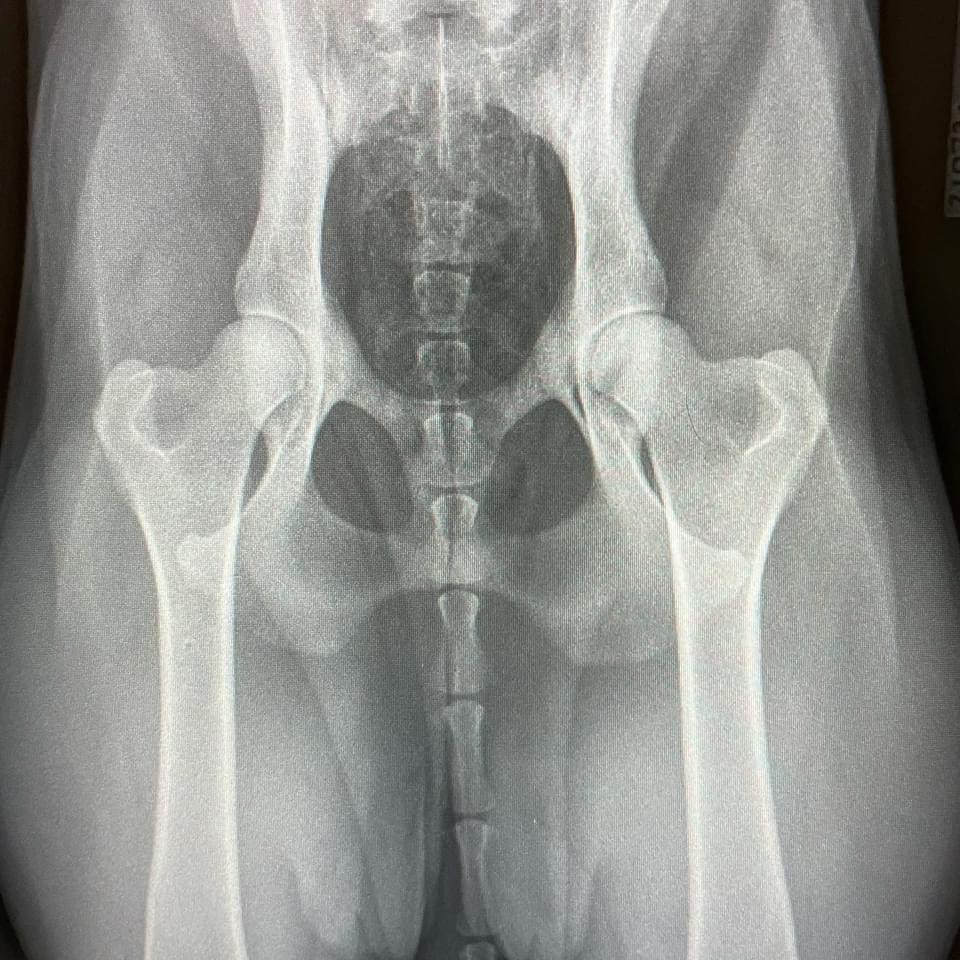

Sjukdomen innebär att höftleden inte utvecklas normalt och vid röntgen graderas felet med graderna C, D eller E (Lindrig, måttlig eller kraftig dysplasi).

En Normal led graderas A eller B.

Bild på en Normal höft med Grad A